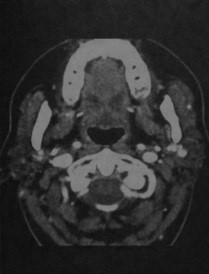

- Диффузное поражение со сниженной плотностью (плотность идентична жидкости) с кистами различных размеров и наличием ячеек, в зависимости от стадии заболевания

- Околоушные железы увеличены, структура ячеистая

Синдром Шегрена. КТ с контрасти рованием: неоднородная плотность паренхимы обеих желез и уменьшение их размеров вследствие фиброза.